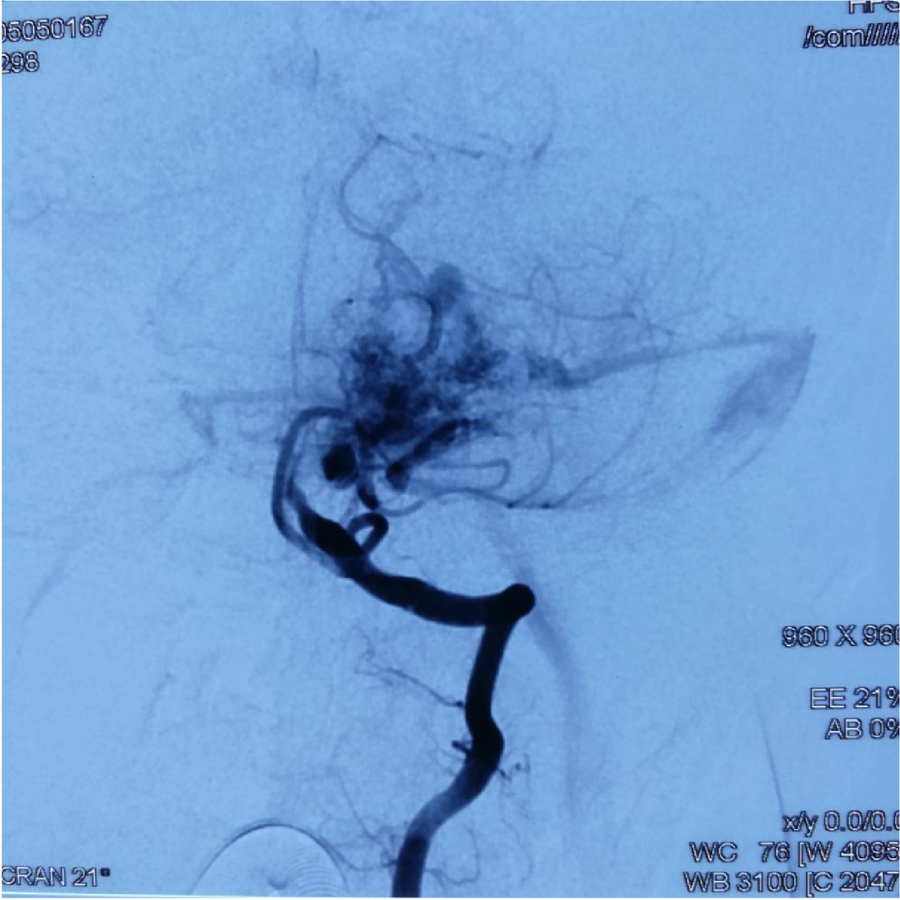

第⼀次DSA显⽰PICA供⾎

引流⾄⼄状窦

小脑后下动脉、小脑前下动脉参与供⾎